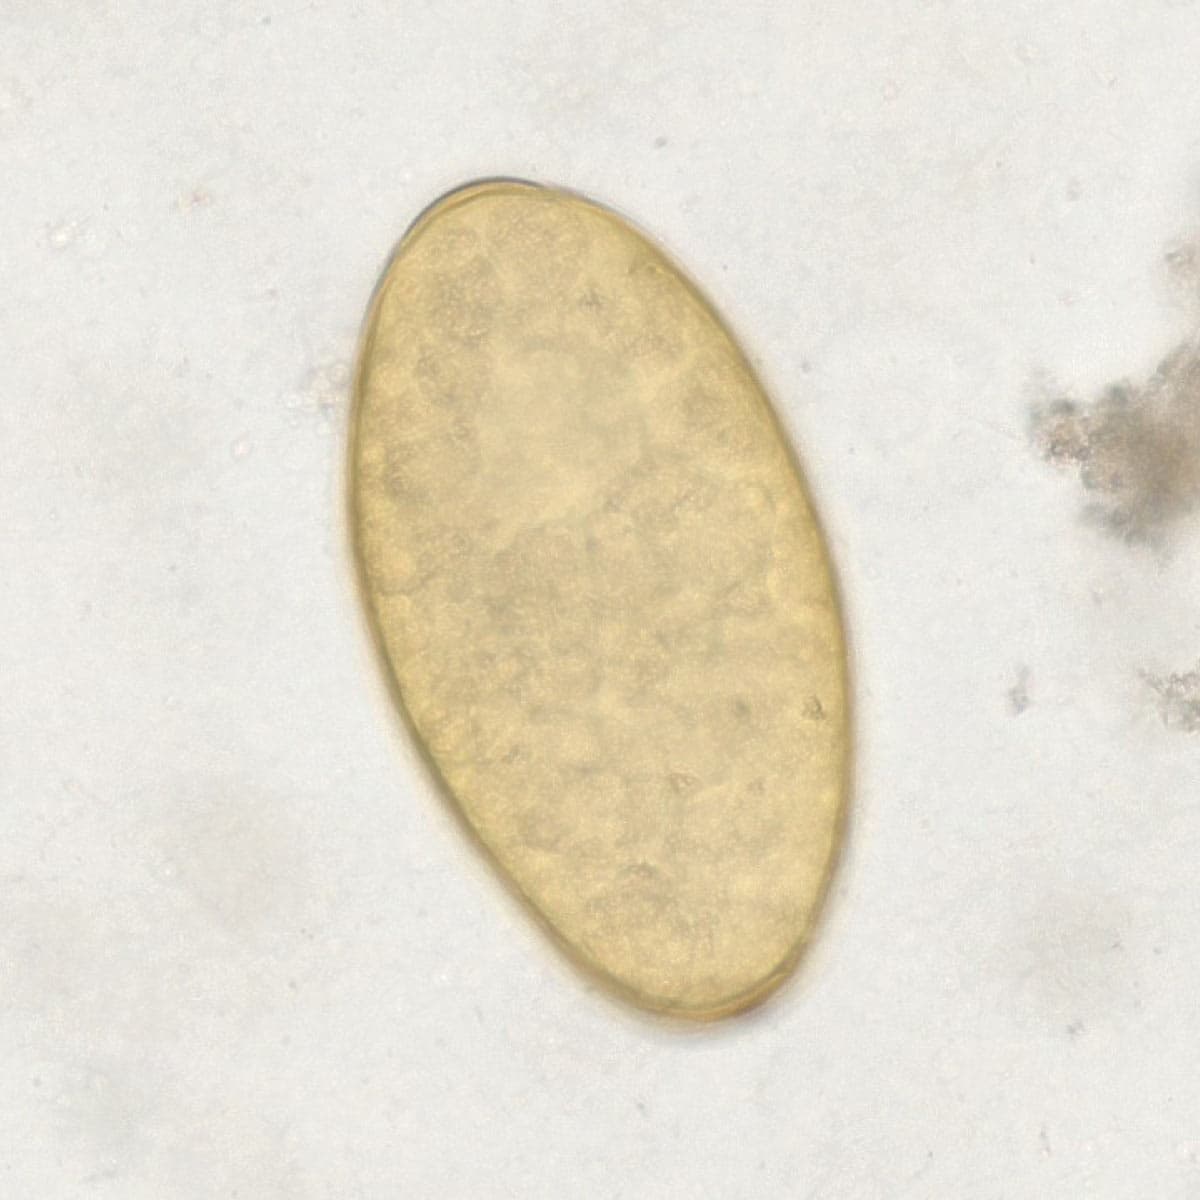

Automatic detection of rare species

Built on worldwide parasite-positive specimens, ParaScout AI identifies a vast number of parasite species, including those that are clinically rare or challenging to find.